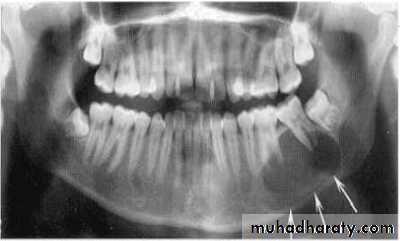

• - Epicenter of the lesion is above the mandibular canal-odontogenic in origin .

• - Epicenter -below lDC- non odontogenic

• - Cartilaginous lesion, osteochondroma –condylar region

• - If the epicenter of the lesion is in the sinus, non odontogenic .

principles of radiographic interpretation

Cystic ameloblastoma displaced IDC (odontogenic origin)

Epicenter coronal to tooth

(odontogenic epithelium )

• A lesion (developmental salivary gland

• defect) below the IAC

• (non- odontogenic origin).